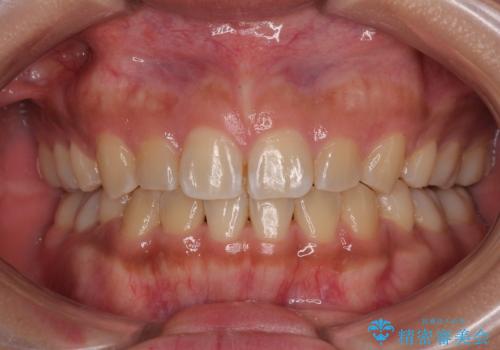

捻れて前に出ている前歯 ワイヤー装置での非抜歯矯正